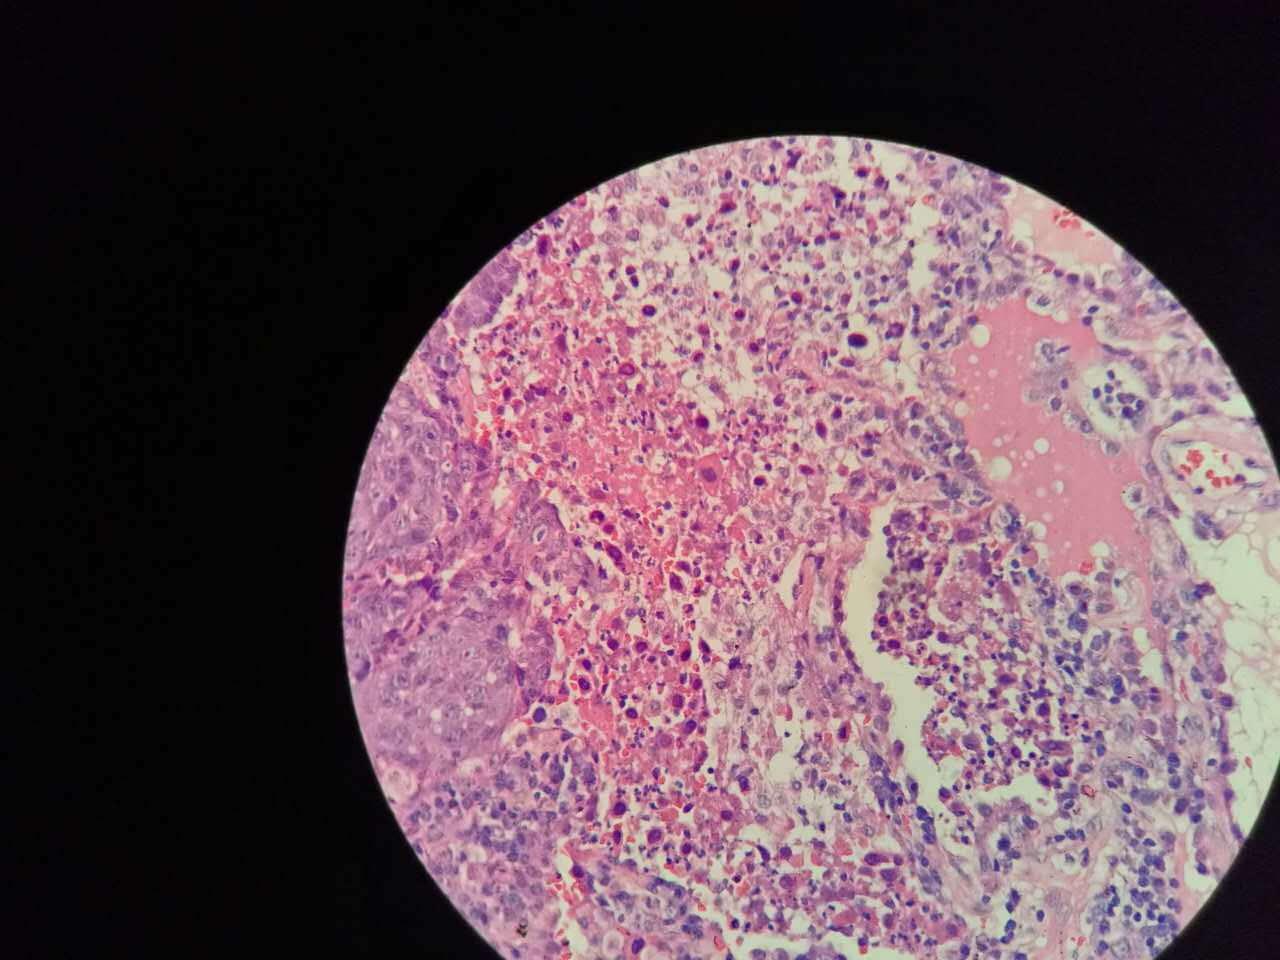

非角化型鳞癌

细胞胖胖的,核大而淡染

也是巢团状,也容易坏死

与实体型腺癌有时难区分,做免疫组化鉴别

左边坏死挺多

红染的,核没了

特征不明显

这是一般的鳞癌,坏死大

一侧常有突起,也就是壁结节。

壁结节不必等到空洞形成才判断,有坏死区就可以在增强片上判断有无壁结节

这个中央那块也算是小型的壁结节,肿瘤组织突入坏死区。或者说,这块肿瘤组织没坏死。